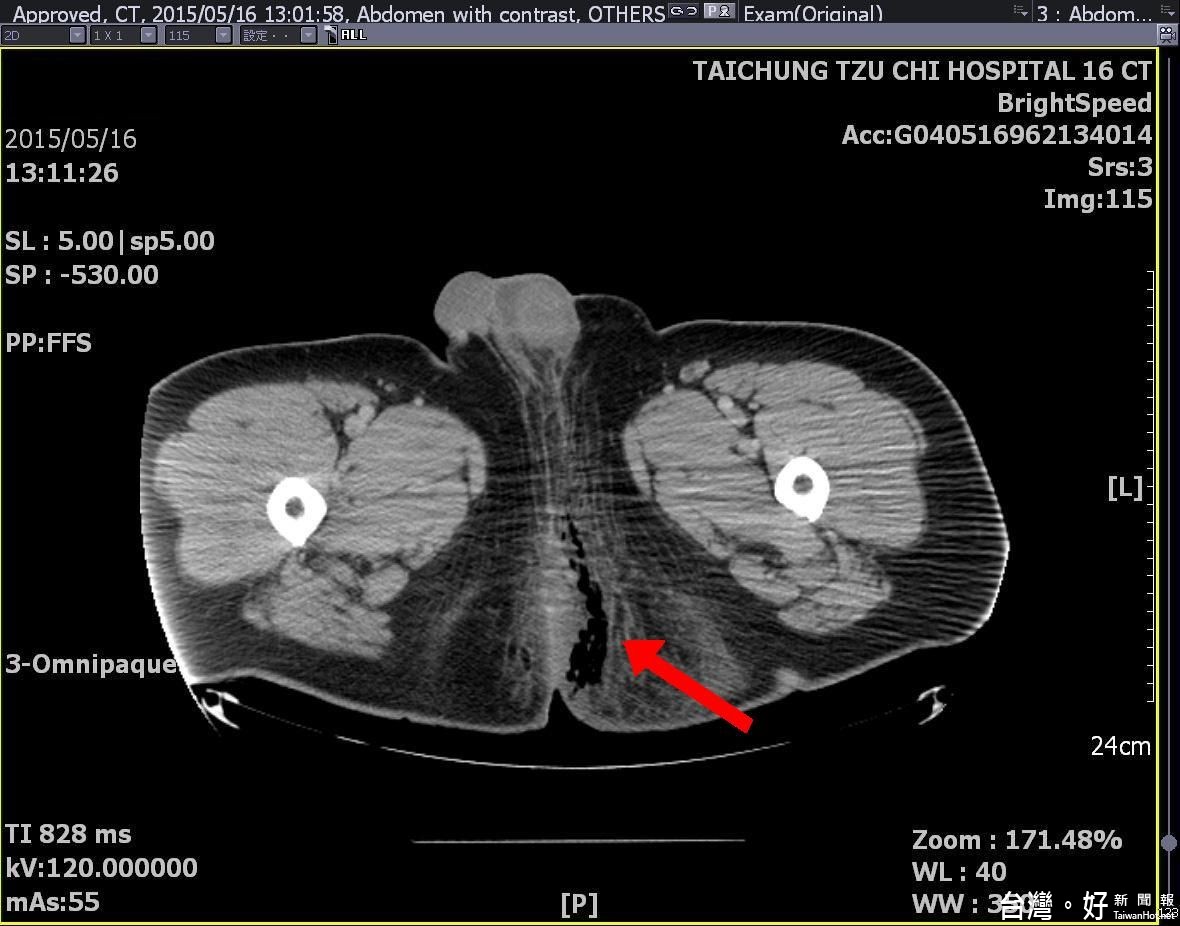

在各科專家團隊努力下,外科加護病房江俊廷主任帶領團隊積極治療三周,經歷八次清創手術、高壓氧加上抗生素治療,才能在狀況改善後轉到普通病房。安排如此頻繁的清創手術和高壓氧積極治療,為的是保命。謝登富醫師表示,進開刀房檢查,才能看見距肛門口不到一公分位置,有個小傷口,細菌一路延伸往內到攝護腺,轉到睪丸附近再向上走,真的擔心萬一清創手術範圍不夠,細菌會蔓延,因此一再清創後,形成超過卅公分、又深又大的傷口,幾乎整個拳頭都能伸進去,病患還要熬過三次插管,泌尿科、大腸直腸科加上整形外科醫師聯手,一路把感染部位全部清乾淨,再完好修補傷口。